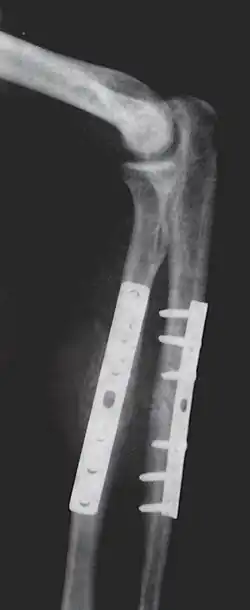

Internal fixation is an operation in orthopedics that involves the surgical implementation of implants for the purpose of repairing a bone, a concept that dates to the mid-nineteenth century and was made applicable for routine treatment in the mid-twentieth century.[1] An internal fixator may be made of stainless steel, titanium alloy,[2] or cobalt-chrome alloy.[3]

Open reduction internal fixation (ORIF) involves the implementation of implants to guide the healing process of a bone, as well as the open reduction, or setting, of the bone. Open reduction refers to open surgery to set bones, as is necessary for some fractures. Internal fixation refers to fixation of screws and/or plates, intramedullary rods and other devices to enable or facilitate healing. Rigid fixation prevents micro-motion across lines of fracture to enable healing and prevent infection, which happens when implants such as plates (e.g. dynamic compression plate) are used. ORIF techniques often are used in cases involving serious fractures such as comminuted or displaced fractures or, in cases where the bone otherwise would not heal correctly with casting or splinting alone.